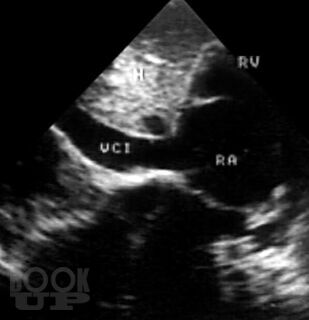

В атласе на большом числе богато иллюстрированных примеров дана эхо- и допплеркардиографическая картина врожденных пороков и ряда заболеваний сердца, а также правила применения методики ультразвукового исследования. Издание восполняет дефицит информации об ультразвуковой диагностике многих сложных врожденных пороков сердца и возможности оценки состояния больных после хирургической коррекции порока.